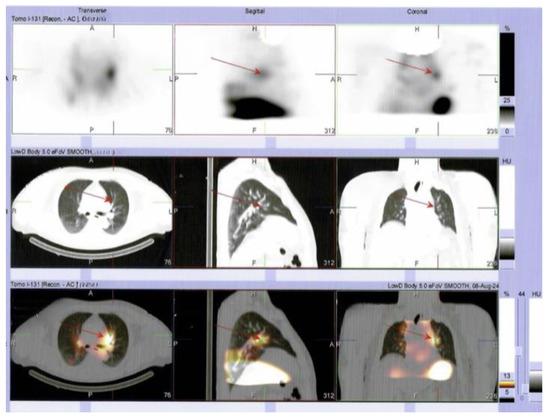

Multilayered Insights into Poorly Differentiated, BRAFV600E-Positive, Thyroid Carcinoma in a Rapidly Developing Goiter with Retrosternal Extension: From En “Y” Cervicotomy to SPECT/CT-Positive Lung Metastases

Sima, O.-C.; Cucu, A.-P.; Terzea, D.; Nistor, C.; Vasilescu, F.; Eftimie, L.-G.; Ciobica, M.-L.; Costachescu, M.; Carsote, M. Multilayered Insights into Poorly Differentiated, BRAFV600E-Positive, Thyroid Carcinoma in a Rapidly Developing Goiter with Retrosternal Extension: From En “Y” Cervicotomy to SPECT/CT-Positive Lung Metastases. Diagnostics 2025, 15, 2049. https://doi.org/10.3390/diagnostics15162049